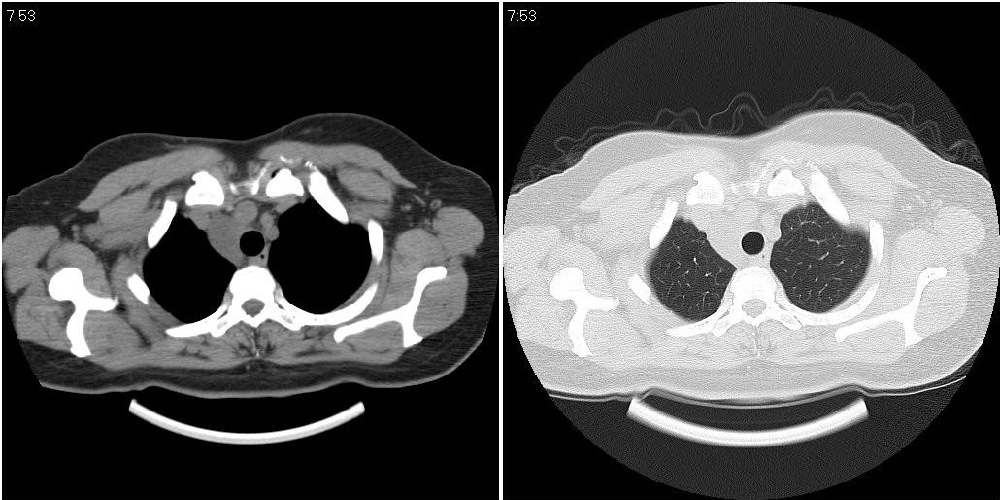

标题: CT24795:女性,47岁,右下腿静脉静脉曲张手术前体检,发现 [打印本页]

标题: CT24795:女性,47岁,右下腿静脉静脉曲张手术前体检,发现

囊性无明显占位效应:1淋巴管囊肿2畸胎瘤(其上部见小钙化)3前肠囊肿

右上纵隔囊性占位性病变;考虑淋巴管囊肿,不排除支气管囊肿。

支气管囊肿、囊性畸胎瘤、肠源性囊肿均有可能。

右上纵隔囊性占位性病变;考虑淋巴管囊肿,不排除支气管囊肿。 建议增强。

考虑淋巴管囊肿,不排除前肠囊肿。